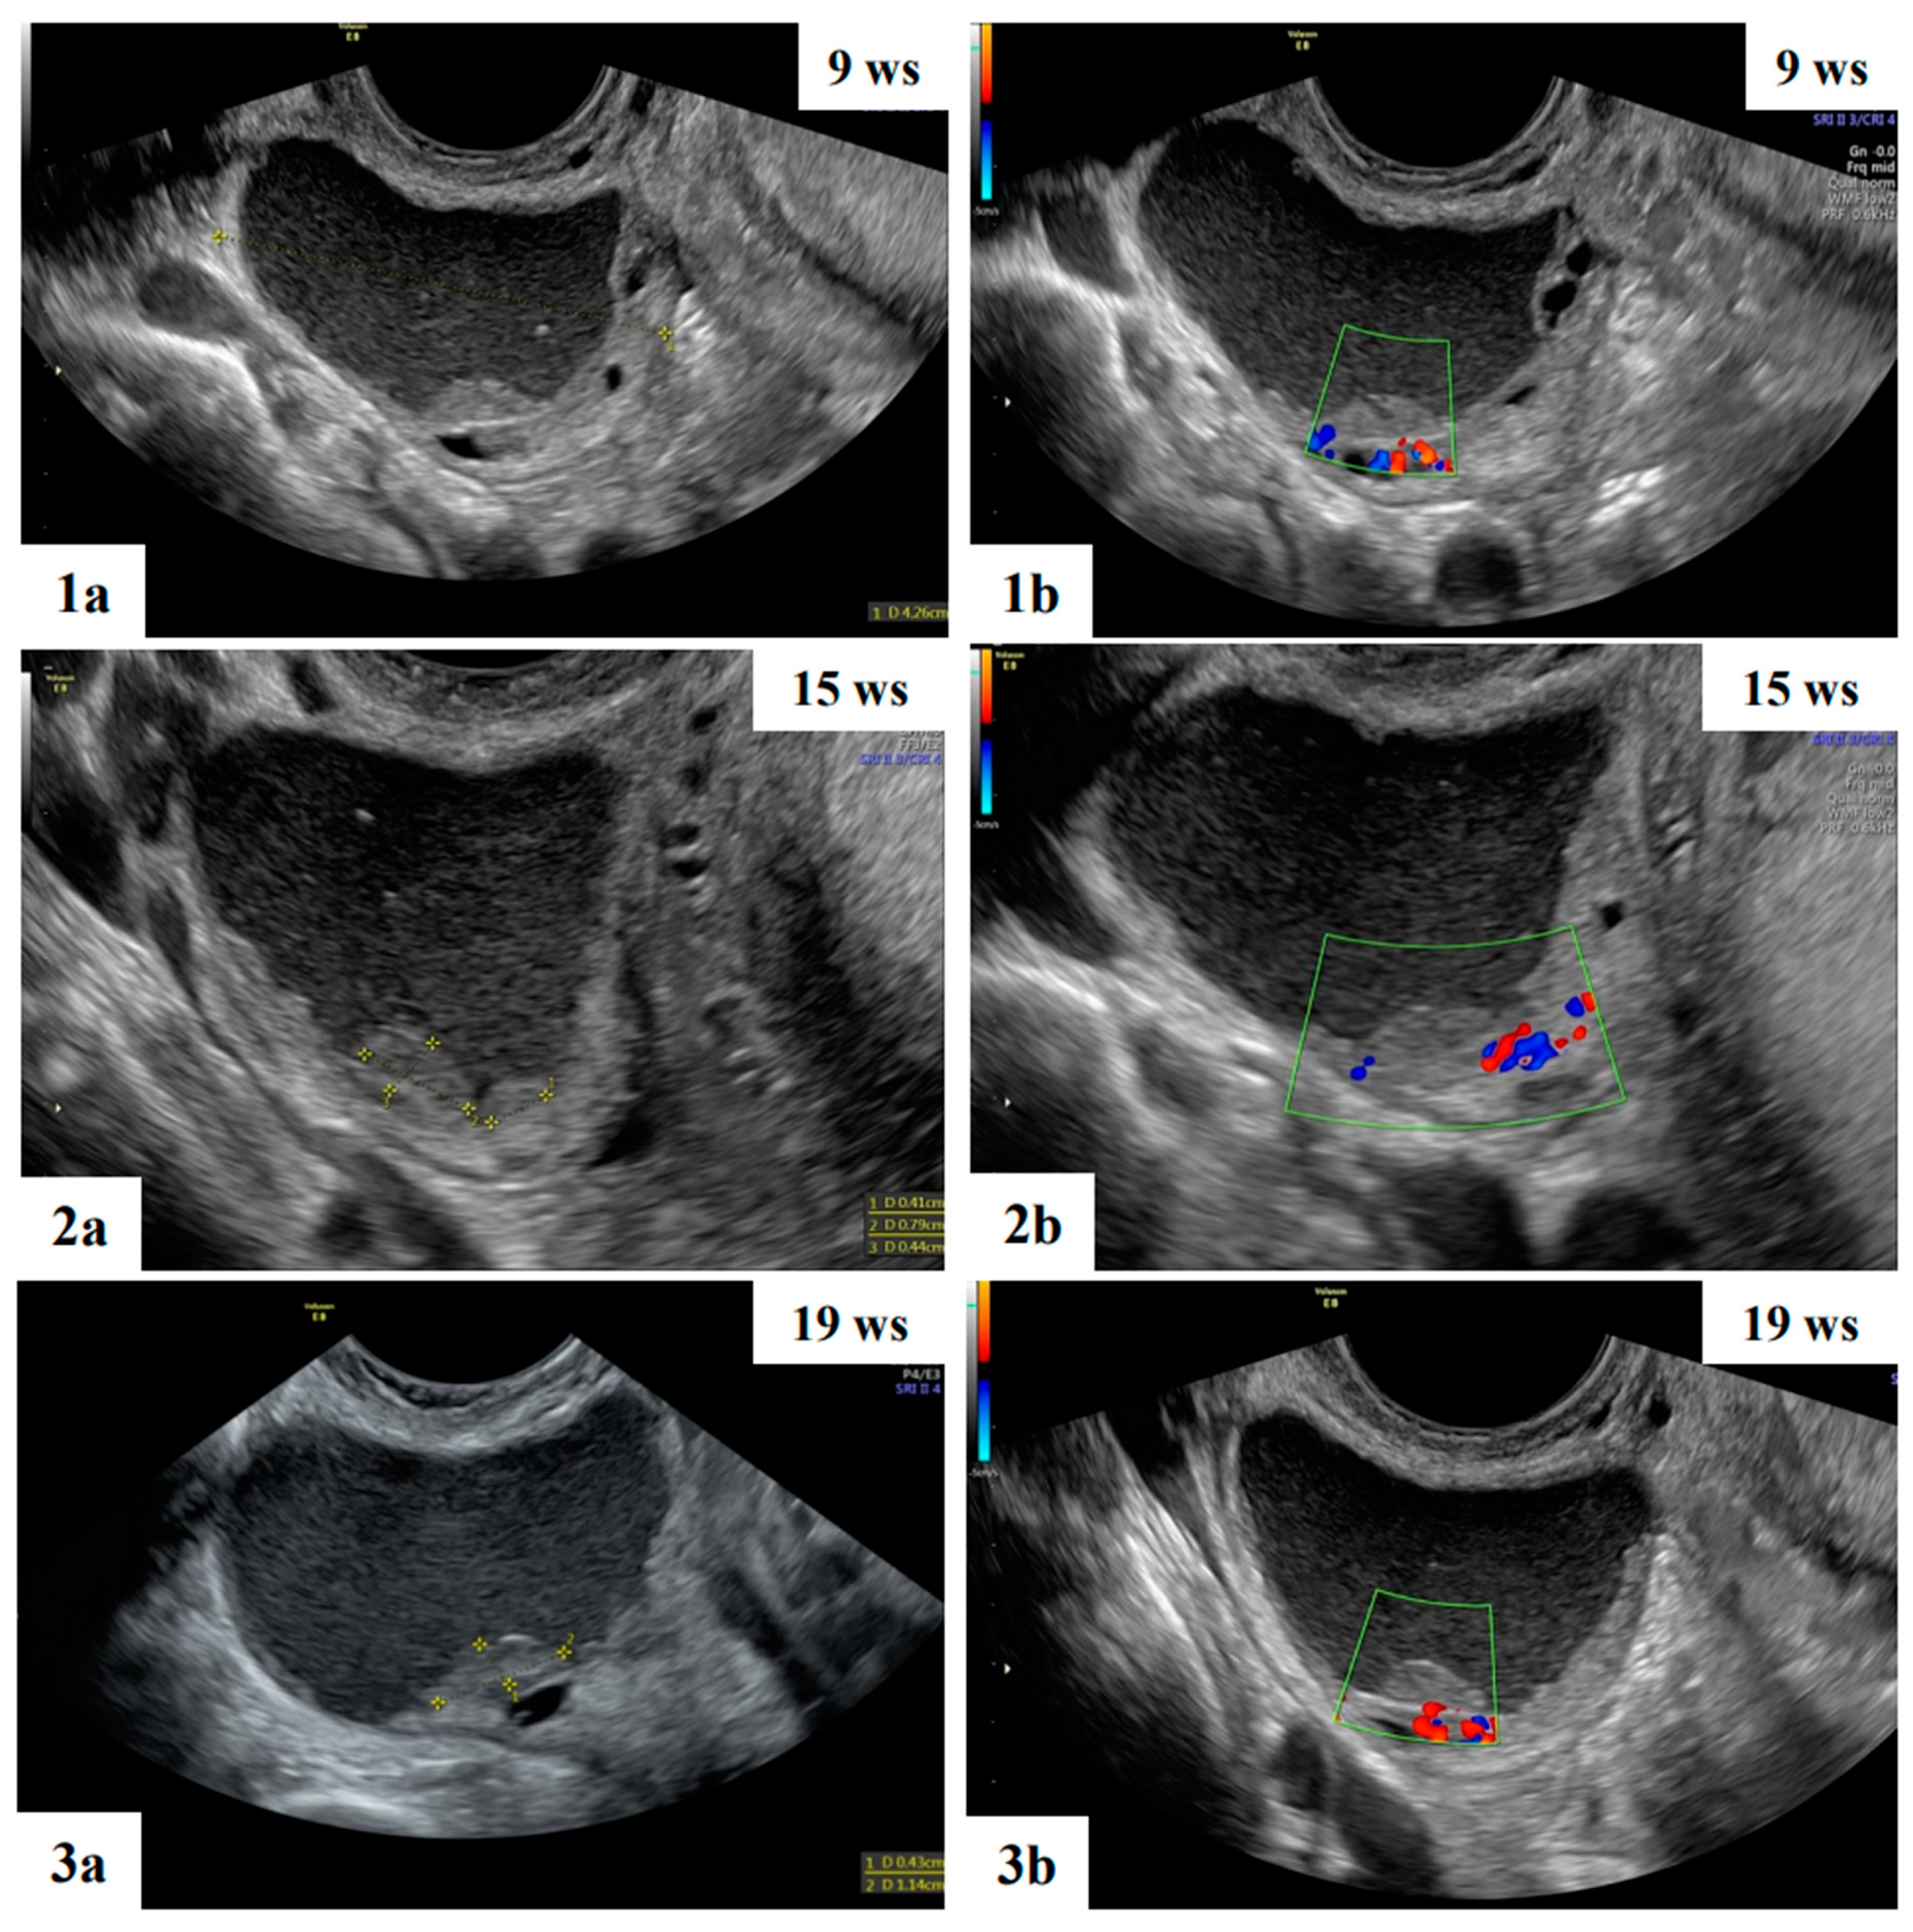

- Mascilini, F.; Moruzzi, C.; Giansiracusa, C.; Guastafierro, F.; Savelli, L.; De Meis, L.; Epstein, E.; Timor-Tritsch I., E.; Mailath-Pokorny, M.; Ercoli, A.; Exacoustos, C.; Benacerraf B., R.; Valentin, L.; Testa, A.C. Imaging in gynecological disease. 10: Clinical and ultrasound characteristics of decidualized endometriomas surgically removed during pregnancy. Ultrasound Obstet Gynecol 2014, 44, 354–360. [Google Scholar] [CrossRef]

- Czekierdowski, A.; Stachowicz, N.; Smole ´n, A.; Kluz, T.; Łozi ´nski, T.; Miturski, A.; Kraczkowski, J. Sonographic Assessment of Complex Ultrasound Morphology Adnexal Tumors in Pregnant Women with the Use of IOTA Simple Rules Risk and ADNEX Scoring Systems. Diagnostics 2021, 11, 414. [Google Scholar] [CrossRef] [PubMed]

- Moro, F.; Mascilini, F.; Pasciuto, T.; Leombroni, M.; Destri, M.L.; De Blasis, I.; Garofalo, S.; Scambia, G.; Testa, A.C. Ultrasound features and clinical outcome of patients with malignant ovarian masses diagnosed during pregnancy: experience of a gynecological oncology ultrasound center. Int. J. Gynecol. Cancer 2019, 29, 1182–1194. [Google Scholar] [CrossRef]